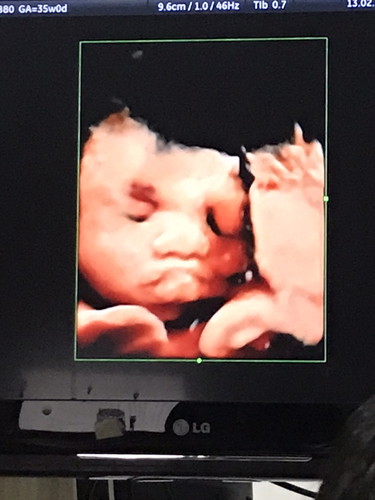

วันนี้เวลา8.30น. กำลังลุกอาบน้ำแต่งตัวไปทำงานแต่มีเลือดไหลเต็มเลยคะ ตอนนั้นกังวลมากทำอะไรไม่ถูกเลยคิดว่าจะเสียลูกไปส่ะแล้ว(ตอนนั้นคือใจสลายร้องไห้ไม่หยุดเลยคะ) คือตอนรู้ว่าท้องไปฝากครรภ์ที่คลินิกและหมอตรวจไม่ละเอียดไม่รู้เลยว่าตัวเองรกเกาะต่ำ จนวันนี้พอมีเลือดออกเราไม่ลีรอเลยคะไป รพ.เอกชน เพราะคิดว่าอยากตรวจไวที่สุดเผื่อจะมีโอกาสช่วยลูก และก็มีโอกาสจริงๆคะหมอตรวจภายในและซาวด์ดู ตอนนี้14weekแล้วคะหัวใจเต้นดีและฉีดยากันแท้งและนอนพัก7วันคะ เกือบเสียลูกไปเพราะวางใจมากเกินไป เหตุการณ์ครั้งนี้ทำให้เราระวังตัวเองมากขึ้นไปอีก ฝากถึงแม่ๆที่กำลังตั้งครรภ์นะคะหากมีเลือดออกหรืออะไรผิดปกติไปพบแพทย์ทันทีเพื่อลูกของเราคะ ตอนนี้สบายใจขึ้นมากแล้วคะ เหลือแต่ระวังตัวและดูแลตัวเองให้มากๆ(ตอนท้องแรกๆหนูทำงานปกตินะคะ) ตอนนี้คงต้องพักยาวๆ เป็นกำลังใจให้แม่ๆทุกๆคนนะคะ✌?☺️? #คุณหมอแซวมาว่าน่าจะเป็นผู้ชายรอลุ้นอีกทีตอน5mคะ ว่าได้เพศอะไร❤️??